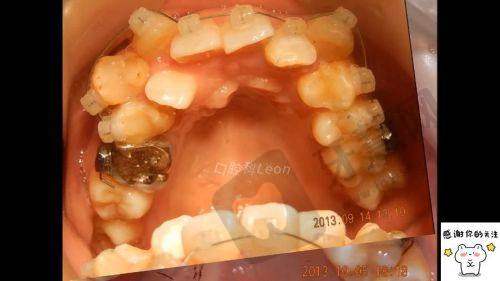

牙齿早期矫治实例:还有一位青少年患者牙齿排列不齐,陈明医生为其制定了牙齿早期矫治方案,通过佩戴合适的矫治器,一段时间后牙齿逐渐变得整齐美观,患者和家长都十分满意。